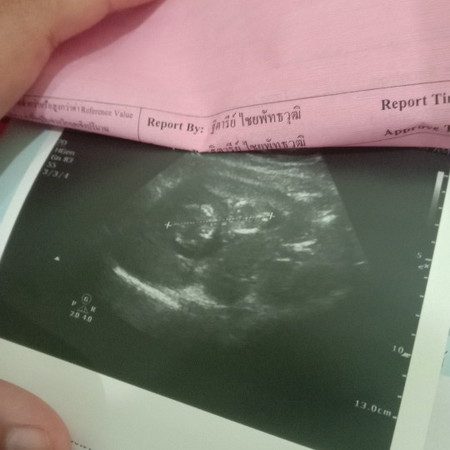

ดูรูปอันตร้าซาว์ไม่เป็น555

รบกวนช่วยดูหน่อยค่ะแม่ๆ555คือเราท้องแรกแล้วรู้สึกตื่นเต้นมากๆแต่ไม่รู้จริงๆว่าเป็นยังไงรบกวนด้วยนะคะ55

ของเราหมอบอกน้องนอนหันหลังให้เห็นแต่หัวหลังก้น11+5Wคะ

ส่วยหัวอยู่ทางขวามือค่ะ ที่มีรอยx--------xนั่นแหละค่ะตัวเด็ก